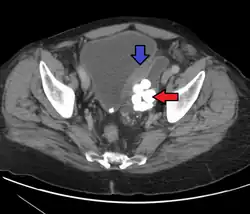

| Histopathology of transitional carcinoma of the urinary bladder. Transurethral biopsy. Hematoxylin and eosin stain. | |